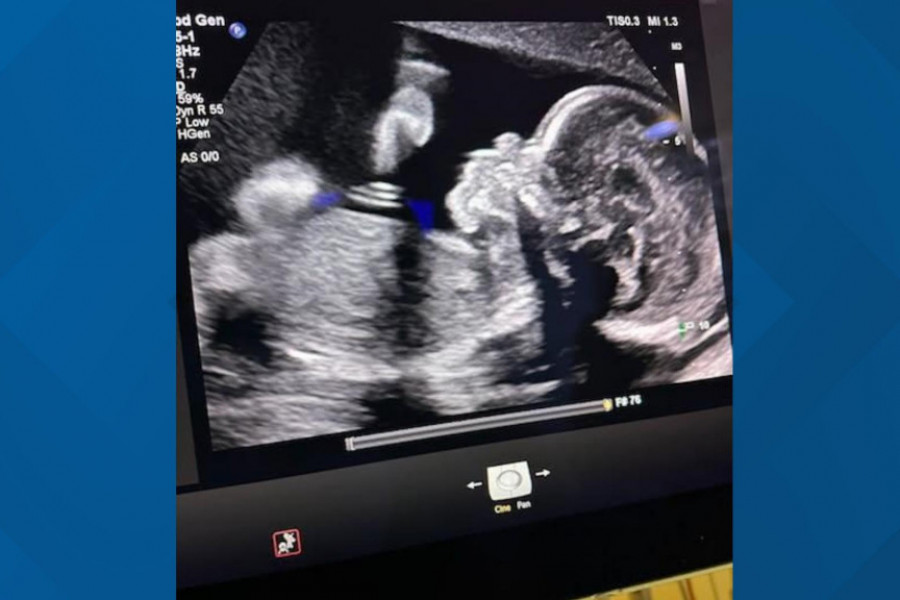

Adriana Smit, 30-godišnja medicinska sestra iz Atlante, proglašena je moždano mrtvom pre više od 90 dana, ali je i dalje održavana na aparatima zbog trudnoće. Njena porodica dovodi u pitanje zakon o "otkucajima srca" u Džordžiji i zašto nisu imali pravo glasa u njenoj nezi.

Trenutno, Smit je 21 nedelju trudna, a lekari planiraju da je održe na aparatima do 32. nedelje trudnoće, kada bi fetus mogao da preživi van materice. Međutim, porodica je zabrinuta zbog zdravstvenog stanja fetusa, jer je primećena tečnost u mozgu.